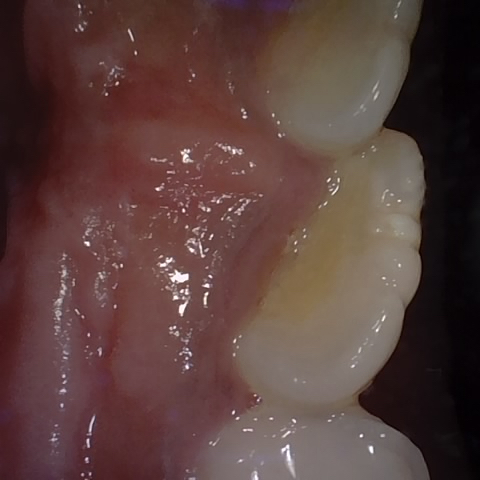

Annotated as "Good"